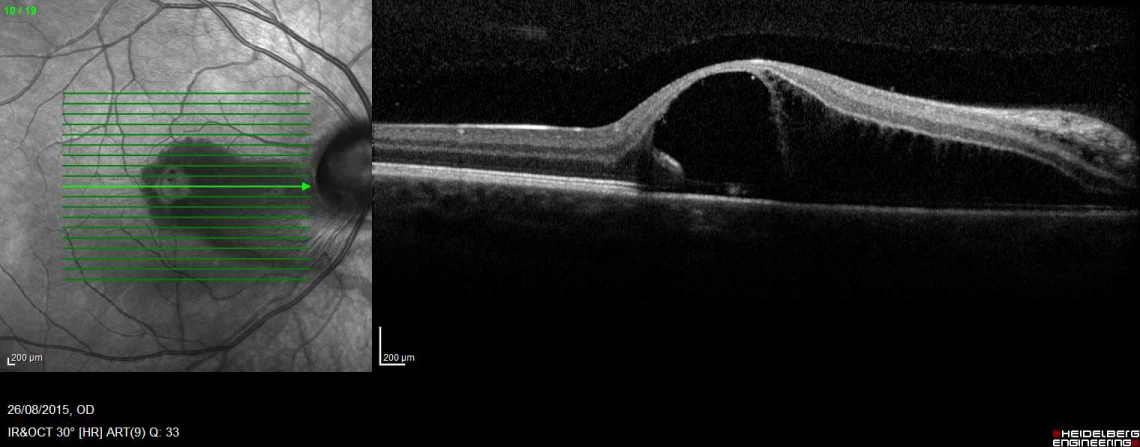

CASE STUDY: Optic Nerve Pit with sub retinal fluid

This is a photo of a 17 year old female I saw last week. This is an Optic Nerve Pit with sub retinal fluid. It is a congenital condition.

She presented with a 3 day history of blur and distortion in the right eye, with the blurring and distortion moving to the central part of her visual field 1 day ago. She presents acuities of the right 6/90, no improvement with pinhole and the left 6/6.

Normally, an isolated optic nerve pit would not call for any treatment. However, due to the sub-retinal fluid, this patient will require a vitrectomy. I’ll keep you updated on their progress.